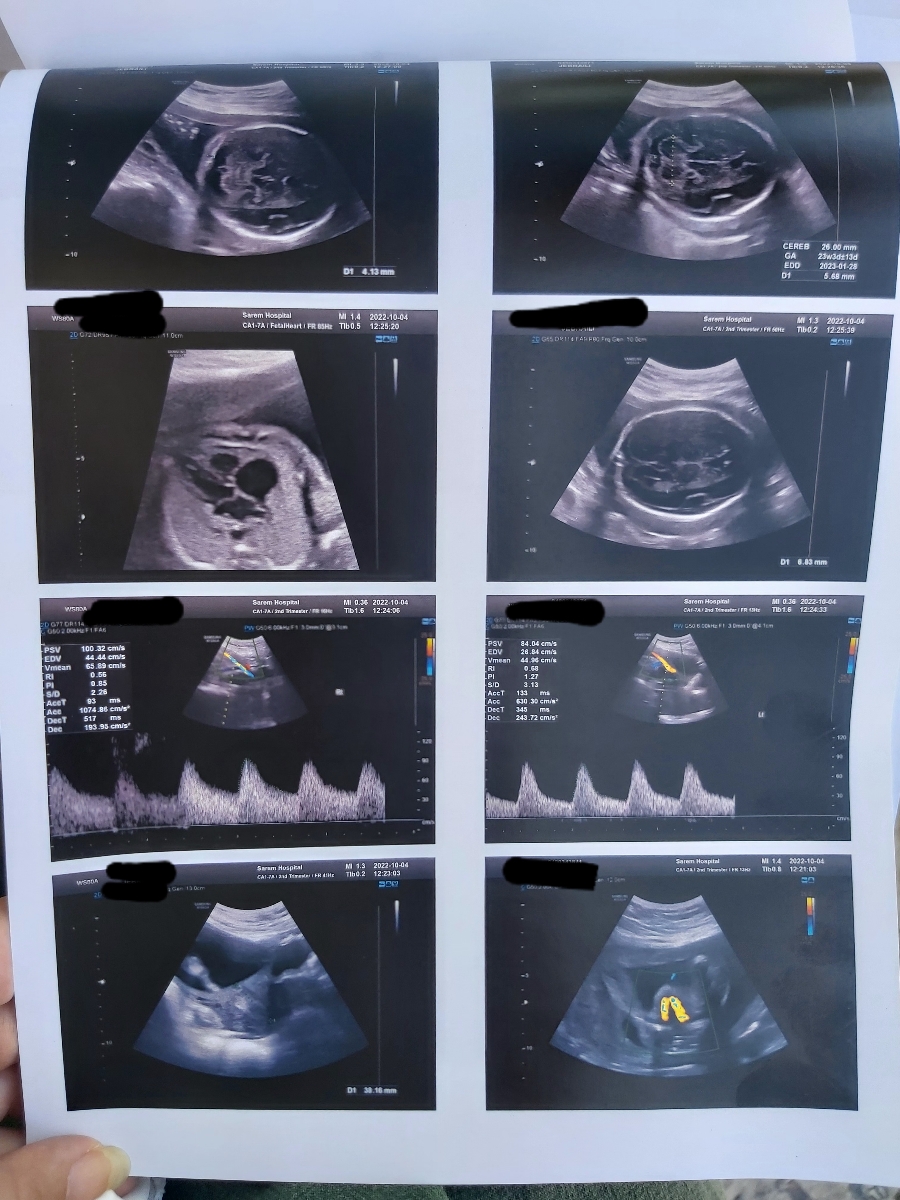

در سونوگرافی شما تمام موارد بررسی شده طبیعی هستند

1. یک دور گردش بند ناف دور گرد دیده شده که از آنجا که بند ناف اندامی نرم و بلند است مشکلی ایجاد نمیشود فقط باید از حرکات ناگهانی اجتناب کرده و مراقب حرکات جنین باشید.

2. یک فیبروم در رحم دیده شده که ابعاد آن مشکل ساز نبوده و فقط روند تغییرات آن در سونوگرافی باید تحت نظر باشد.

3. خونرسانی در داپلر خوب است اما بهتر است با نظر متخصص خود انوکساپارین یا آسپرین را شروع کنید. تصميم نهایی با پزشک شما است.

4. خوشبختانه شواهدی به نفع NTDS وجود ندارد.

در مورد چسبندگی شواهدی دیده نشده است. میتوان با صلاحدید پزشک در هفته های بعدی داپلر را تکرار کرد.

در مورد آنچه سونو به شما گفته شده، کمی مقاومت عروقی سمت چپ دیده شده برای همین من توصیه. به شروع آسپرین یا انوکساپارین داشتم.

بند ناف هم بله گل من با چرخش های جنین ممکن است باز شود و اگر باز نشود هم موردی ندارد نترسید ❤️